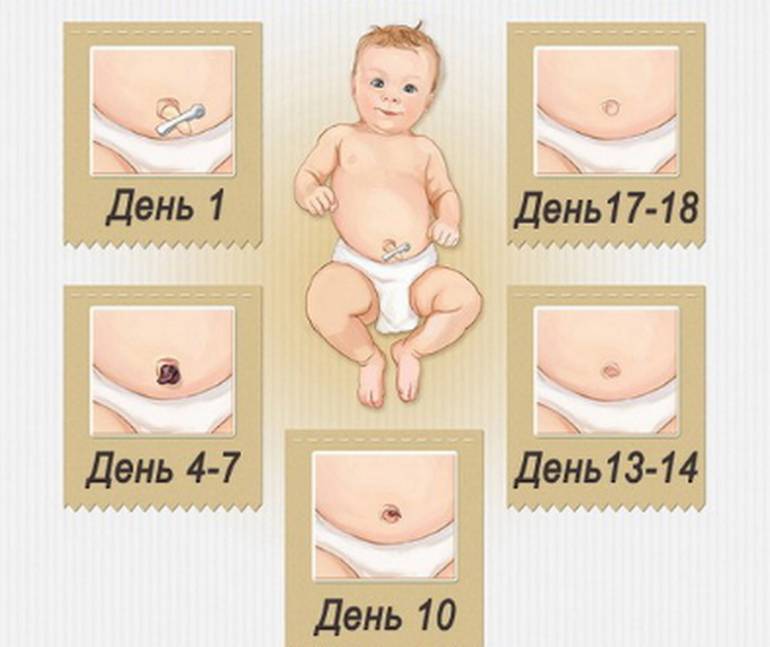

Пупок у новорожденного — сроки заживления пупочной ранки

Брюшные мышцы младенца слабы и недостаточно развиты. Их тренировка начинается с момента рождения ребенка и обрезания пуповины. Когда культя отпадет, маме следует внимательно наблюдать за крохой: